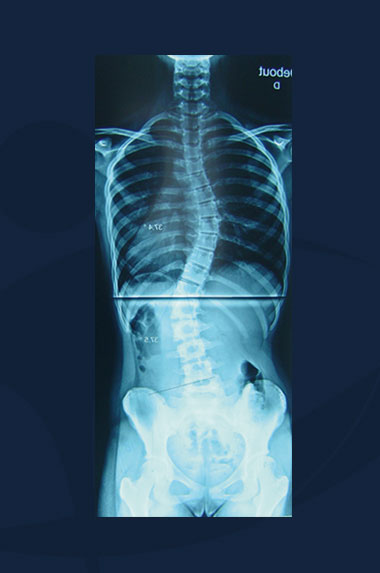

Lynda Smith

Clichés radiologiques du rachis (sans corset).

Scoliose Double